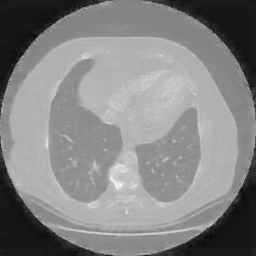

Original NATIVE CT scan (input)

Mediastinum window (WL 40, WW 400 β†’ Low βˆ’160, High +240)

Reconstructed NATIVE CT scan (cycle consistency)

Original VENOUS CT scan

Generated VENOUS CT scan (A→B translation)